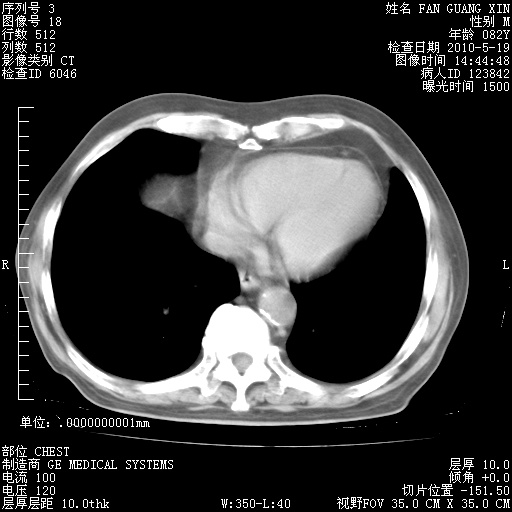

复查肺部CT,明显好转。为什么发热呢?

治疗3周后的肺部CT

治疗3周后的肺部CT纵隔窗